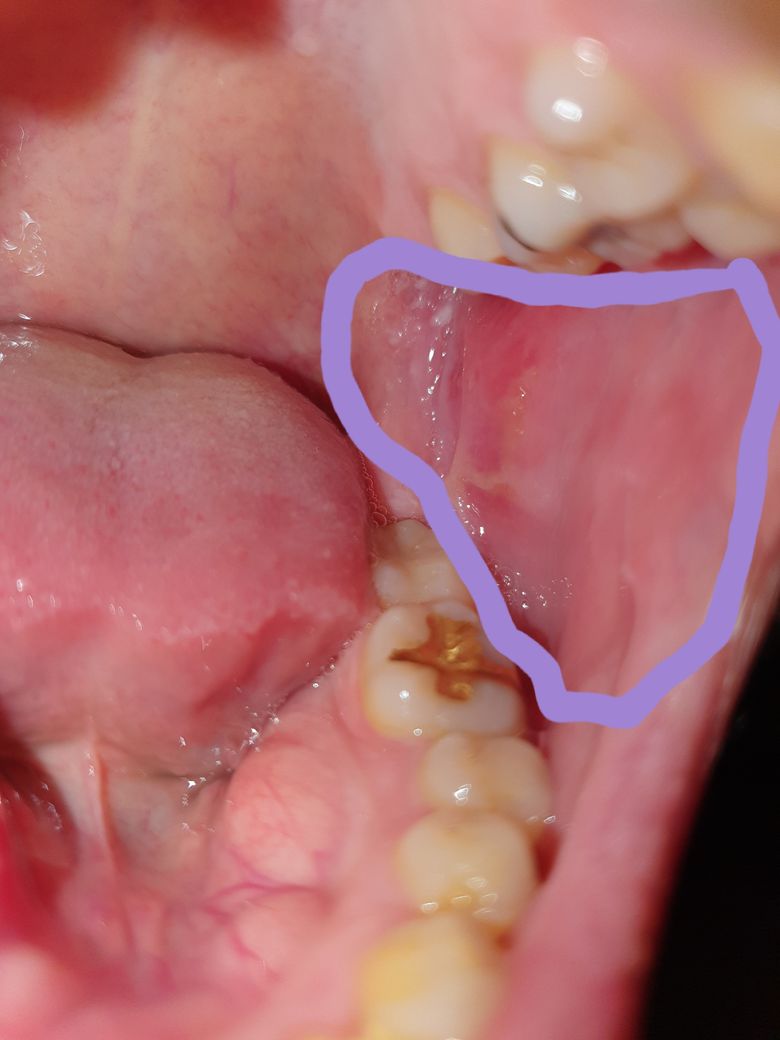

왼쪽 입안에 볼쪽부근이 아파서 질문남깁니다

며칠전부턴가 왼쪽 입안에 볼쪽?이라하나요?

아픕니다

입이 움직일때마다 아픕니다

왜이렇게 아픈가요? 구내염일종인것같기도한것이

진료볼려면어디로가야하나요? 내과 아님 이비인후과가는게 맞나요?

• 1번 째 사진

사진만으로는 정확한 진료가 불가하나 아프타성 구내염의 가능성이 있어 보입니다.

보통 몸이 피곤하시거나 이로 깨무는 등의 기계적 자극이 있을시 이러한 구내염이 생깁니다. 자주 생기며 여러 곳에 생긴다면 베체트 질환과 같은 자가면역 질환도 의심해봐야 합니다.

충분한 수분섭취와 휴식이 필요하며, 일주뒤에도 지속이 된다면 근처 이비인후과 진료보시기 바랍니다. 아울러 자주 이로 깨무는 증상이 있다면 치과에 내원하셔서 상담 받아보시고 교정 등을 고려해보시기 바랍니다.